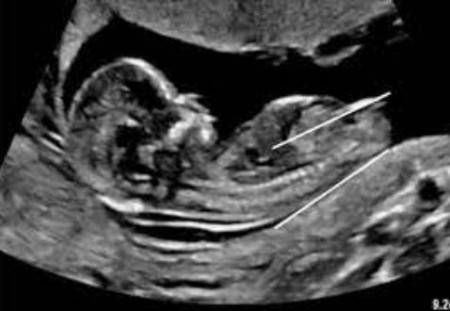

تصاویر سونوگرافی جنین دختر و پسر می‌تواند به والدین در تشخیص جنسیت جنین خود کمک کند. در این تصاویر، معمولاً برآمدگی بین پاهای جنین به عنوان اولین نشانه جنسیت او دیده می‌شود.

سونوگرافی جنین دختر

در سونوگرافی جنین دختر، برآمدگی بین پاها به شکل دو خط تیره نازک دیده می‌شود. این دو خط تیره، لبیاهای بزرگ و کوچک هستند. در برخی موارد، ممکن است یک سپتوم (دیوار نازک) بین دو لبیا دیده شود. این سپتوم می‌تواند باعث شود که لبیا به شکل یک آلت تناسلی مردانه دیده شود.